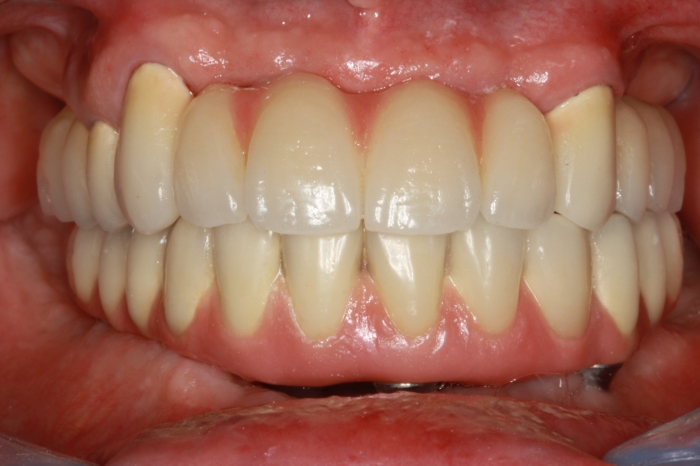

Próteses fixas em porcelana superior e inferior sobre implantes Cone Morse

Sorriso final do caso terminado em 2012